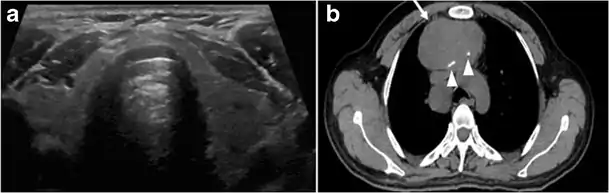

Fig. 7. A 51-year-old female patient post total thyroidectomy for PTC with elevated thyroglobulin measurement. an Axial non-enhanced CT scan of the neck at the level of the thyroid bed demonstrates a well-defined, rounded, homogenously dense soft tissue situated between the trachea and left internal jugular vein (white arrow). b Transverse ultrasound image of the neck demonstrates a well-defined, homogeneous, hypoechoic soft tissue nodule measuring 6 mm (white arrow) with no detected micro-calcifications. Biopsy showed a predominantly residual normal thyroid tissue with micro-foci of PTC.[1]

Fig. 8. A 48-year-old male patient post total thyroidectomy with PTC recurrence. a Transverse greyscale ultrasound of the neck demonstrates a left thyroid bed heterogeneous, predominantly hypoechoic irregular lesion with calcifications (white arrow). b A spot image of iodine 123 total body scan of the neck demonstrate a focus of abnormal radiotracer uptake at the left thyroid bed (Black arrows) between the annotated markers. c Enhanced axial CT scan of the neck demonstrates an enhancing large left thyroid bed mass (white arrow) with no calcifications. The lesion exerts a mass effect on the oesophagus (black arrow) and is inseparable from the trachea.[1]